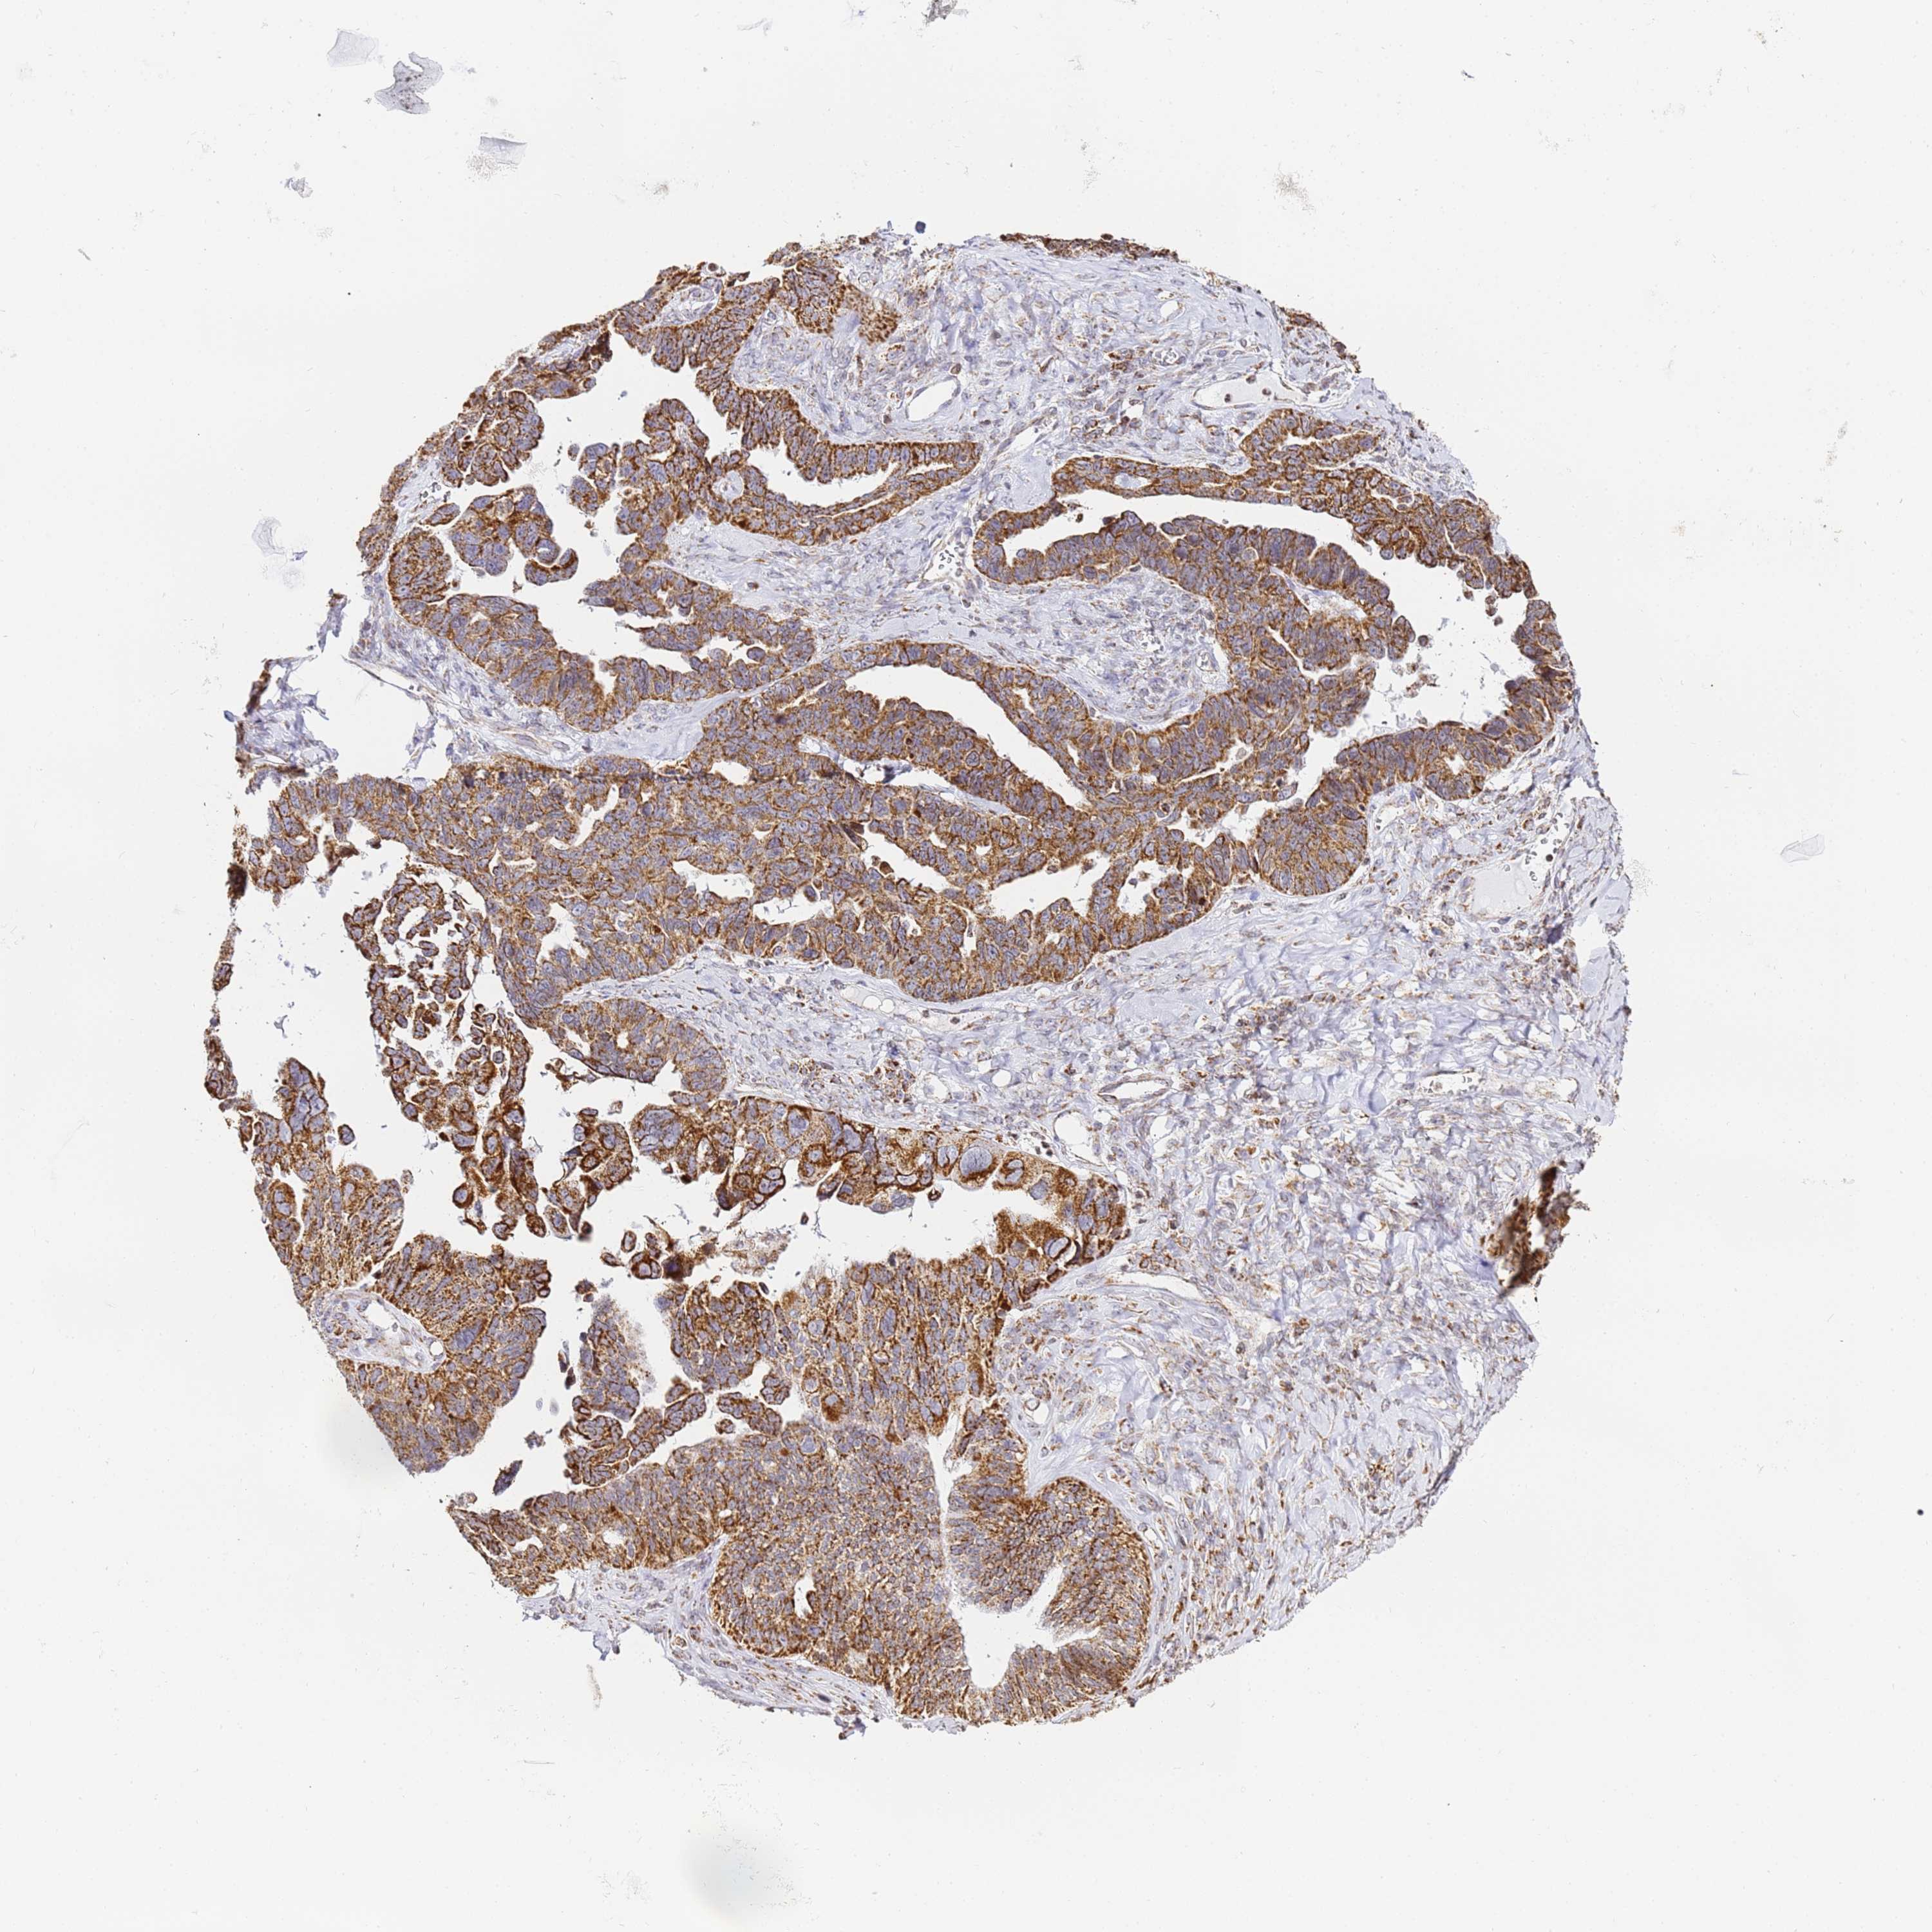

OVARIAN CANCER - Protein expressioni

A mouse-over function shows sample information and annotation data. Click on an image to view it in a full screen mode. Samples can be filtered based on level of antibody staining by selecting one or several of the following categories: high, medium, low and not detected. The assay and annotation is described here.

Note that samples used for immunohistochemistry by the Human Protein Atlas do not correspond to samples in the TCGA dataset.

Antibody stainingi

Antibody staining in the annotated cell types in the current human tissue is reported as not detected, low, medium, or high, based on conventional immunohistochemistry profiling in selected tissues. This score is based on the combination of the staining intensity and fraction of stained cells.

Each image is clickable and will lead to virtual microscopy that enables deeper exploration of all samples and also displays staining intensity scores, fraction scores and subcellular localization as well as patient and tissue information for each sample.

Antibody HPA038755

Antibody HPA044125

Antibody HPA048272

Staining

High

Medium

Low

Not detected

Intensity

Strong

Moderate

Weak

Negative

Quantity

>75%

75%-25%

<25%

None

Location

Nuclear

Cytoplasmic/membranous

Cytoplasmic/membranous,nuclear

Cystadenocarcinoma, serous, NOS

Carcinoma, endometroid

Cystadenocarcinoma, mucinous, NOS

Carcinoma, NOS